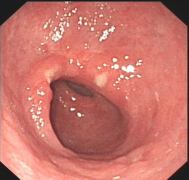

【检查】萎缩性胃炎的检查方法

导语 俗话说十人九胃就是形容胃病患者之多,在所有的胃病当中,萎缩性胃炎

盘锦医生解析:慢性非萎缩性胃炎伴糜烂

导语 慢性非萎缩性胃炎伴糜烂,又称疣状胃炎或痘疹状胃炎,它常和消化性溃